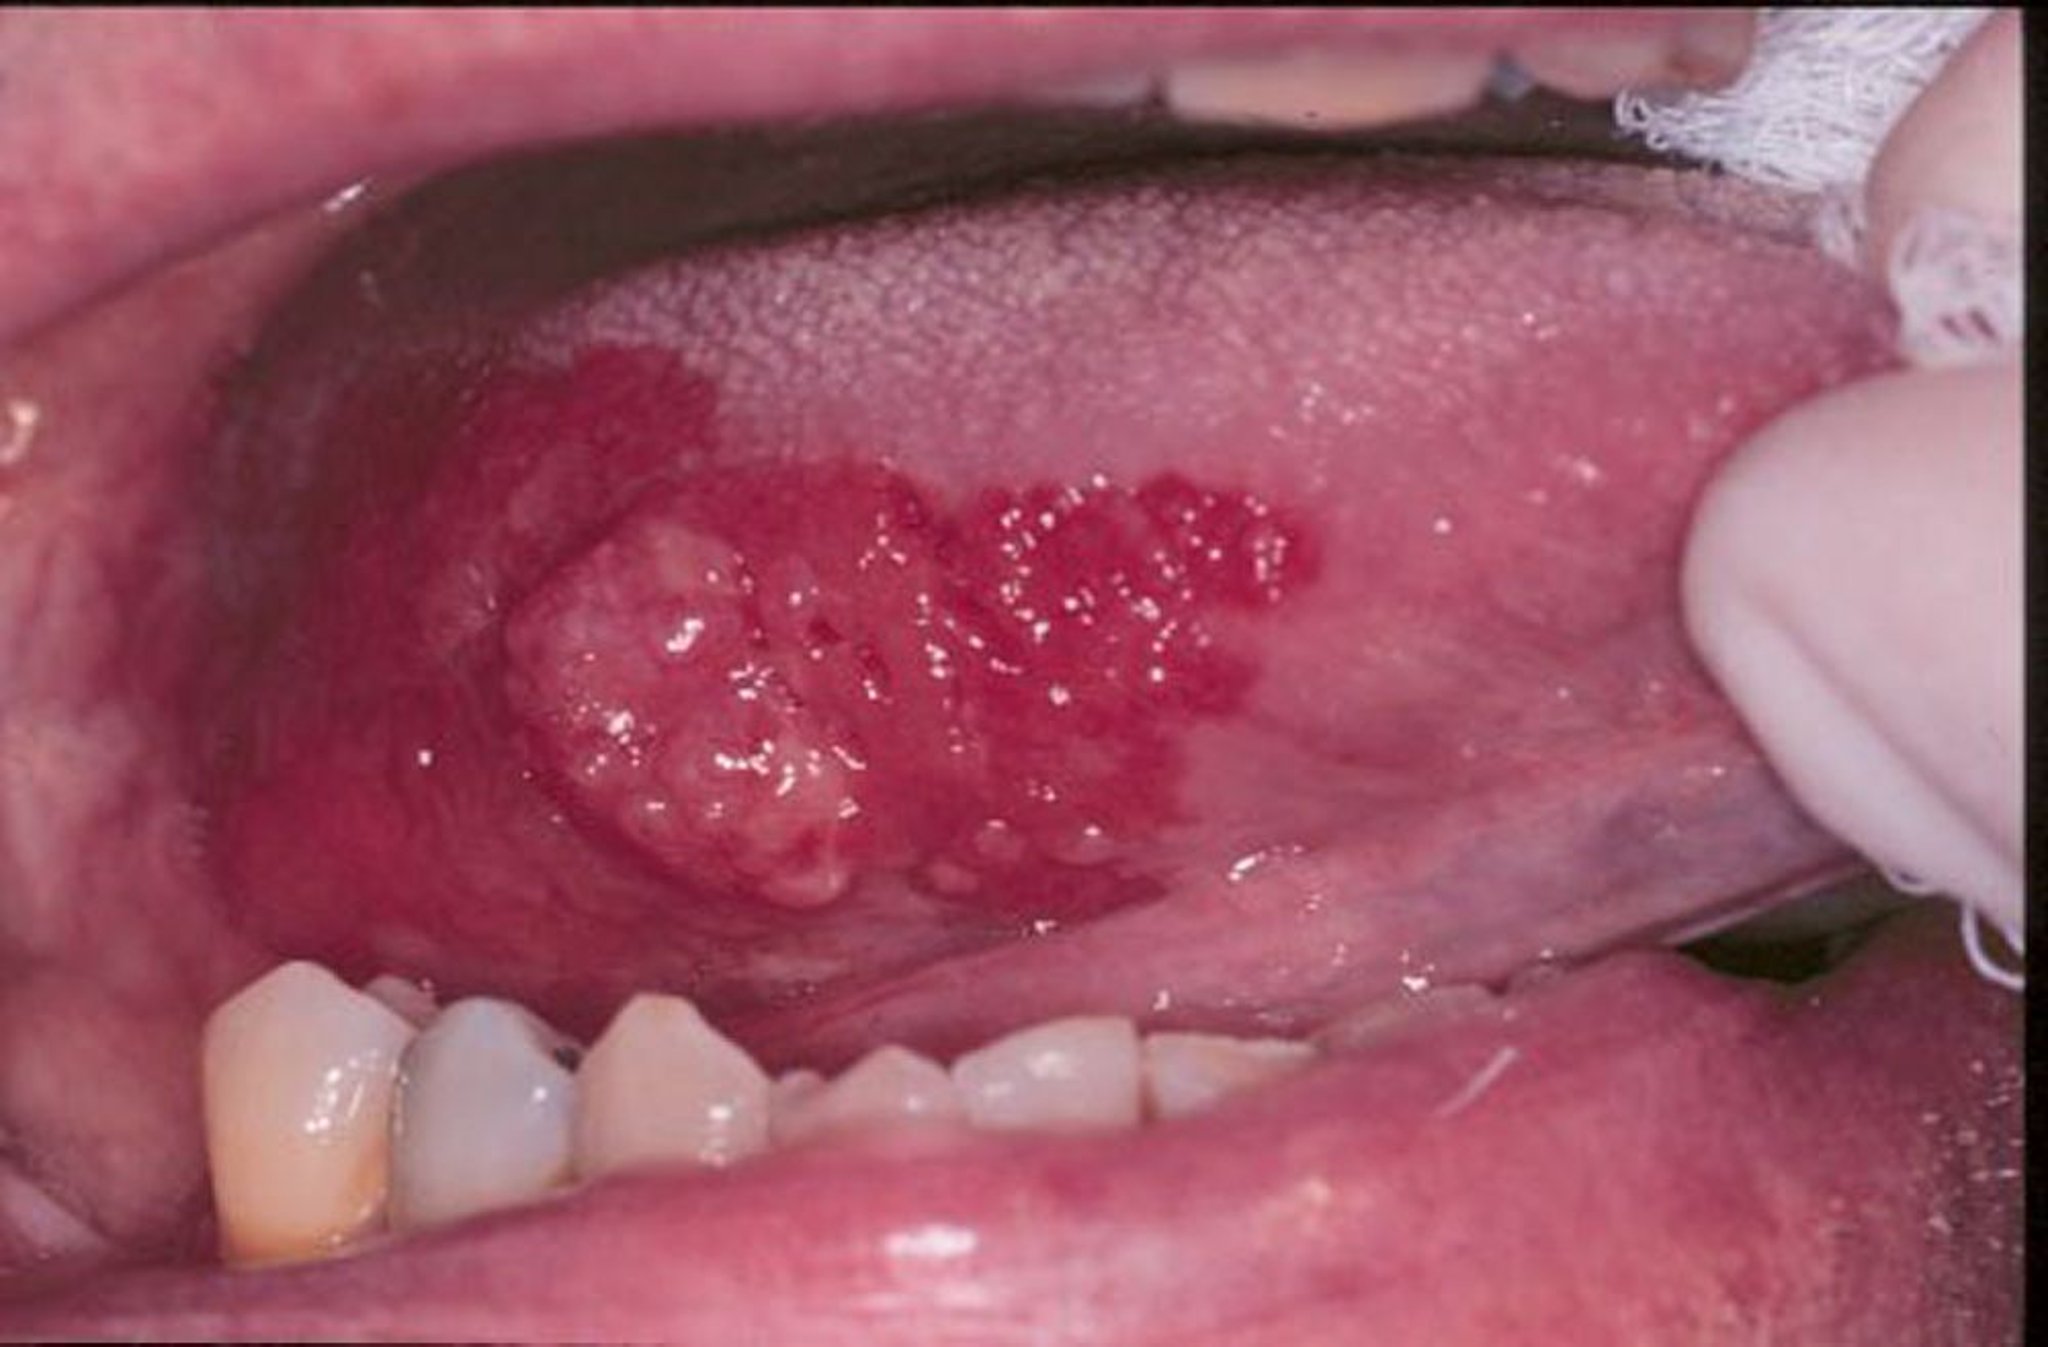

Érythroplasie et carcinome épidermoïde

L’érythroplasie est un terme général pour les ulcères rouges, plats ou dégradés à l’aspect velouté qui se développent dans la bouche. Sur cette image, un carcinome épidermoïde est entouré par une crête d’érythroplasie.

Image fournie par le chirurgien-dentiste Jonathan A. Ship.